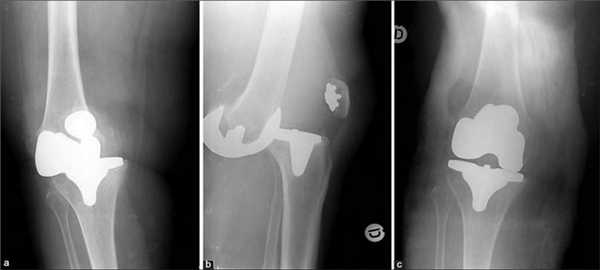

Проведение эндопротезирования считается крайней мерой, назначаемой при невозможности восстановления коленного сустава другими способами. Операцию выполняют чаще всего при артрите, артрозе, серьезных травмах.

Операция по замене коленного сустава является одним из вариантов лечения коленного сустава, поврежденного остеоартритом. Остеоартроз развивается вследствие разрушения суставного хряща и подлежащей кости.

Во время процедуры хирург удалит поврежденный хрящ и кость перед имплантацией искусственного сустава, содержащего металл, пластик и другие синтетические материалы.

Ежегодно в России проводится более 100 тысяч таких операций. Во время процедуры хирург удаляет коленный сустав и заменяет его металлическим, керамическим или пластиковым. Нужно сказать, что сейчас сделать эндопротезирование коленного сустава несложно, и квоты на это государство охотно выделяет.

Рентген после операции. Протез стоит корректно.